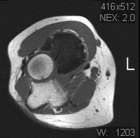

62 y/o female presents with a few months of an increasing left elbow mass, discomfort with activity, relieved by rest

PMH/PSH: Breast cancer treated with lumpectomy, nonsmoker

PE: Large nontender mass anterior L elbow, only a few degrees loss of ROM at elbow, no LAN, neurovasculary intact